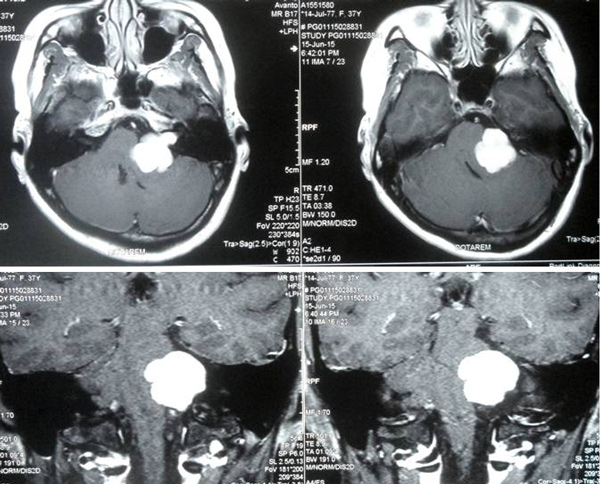

In May 2015, she came to Singapore and consulted an ENT specialist. She was given medication for a month. Her condition worsened. She came back to Singapore again in June and had an MRI.  There was a 3 cm tumour in her brain.

Composite